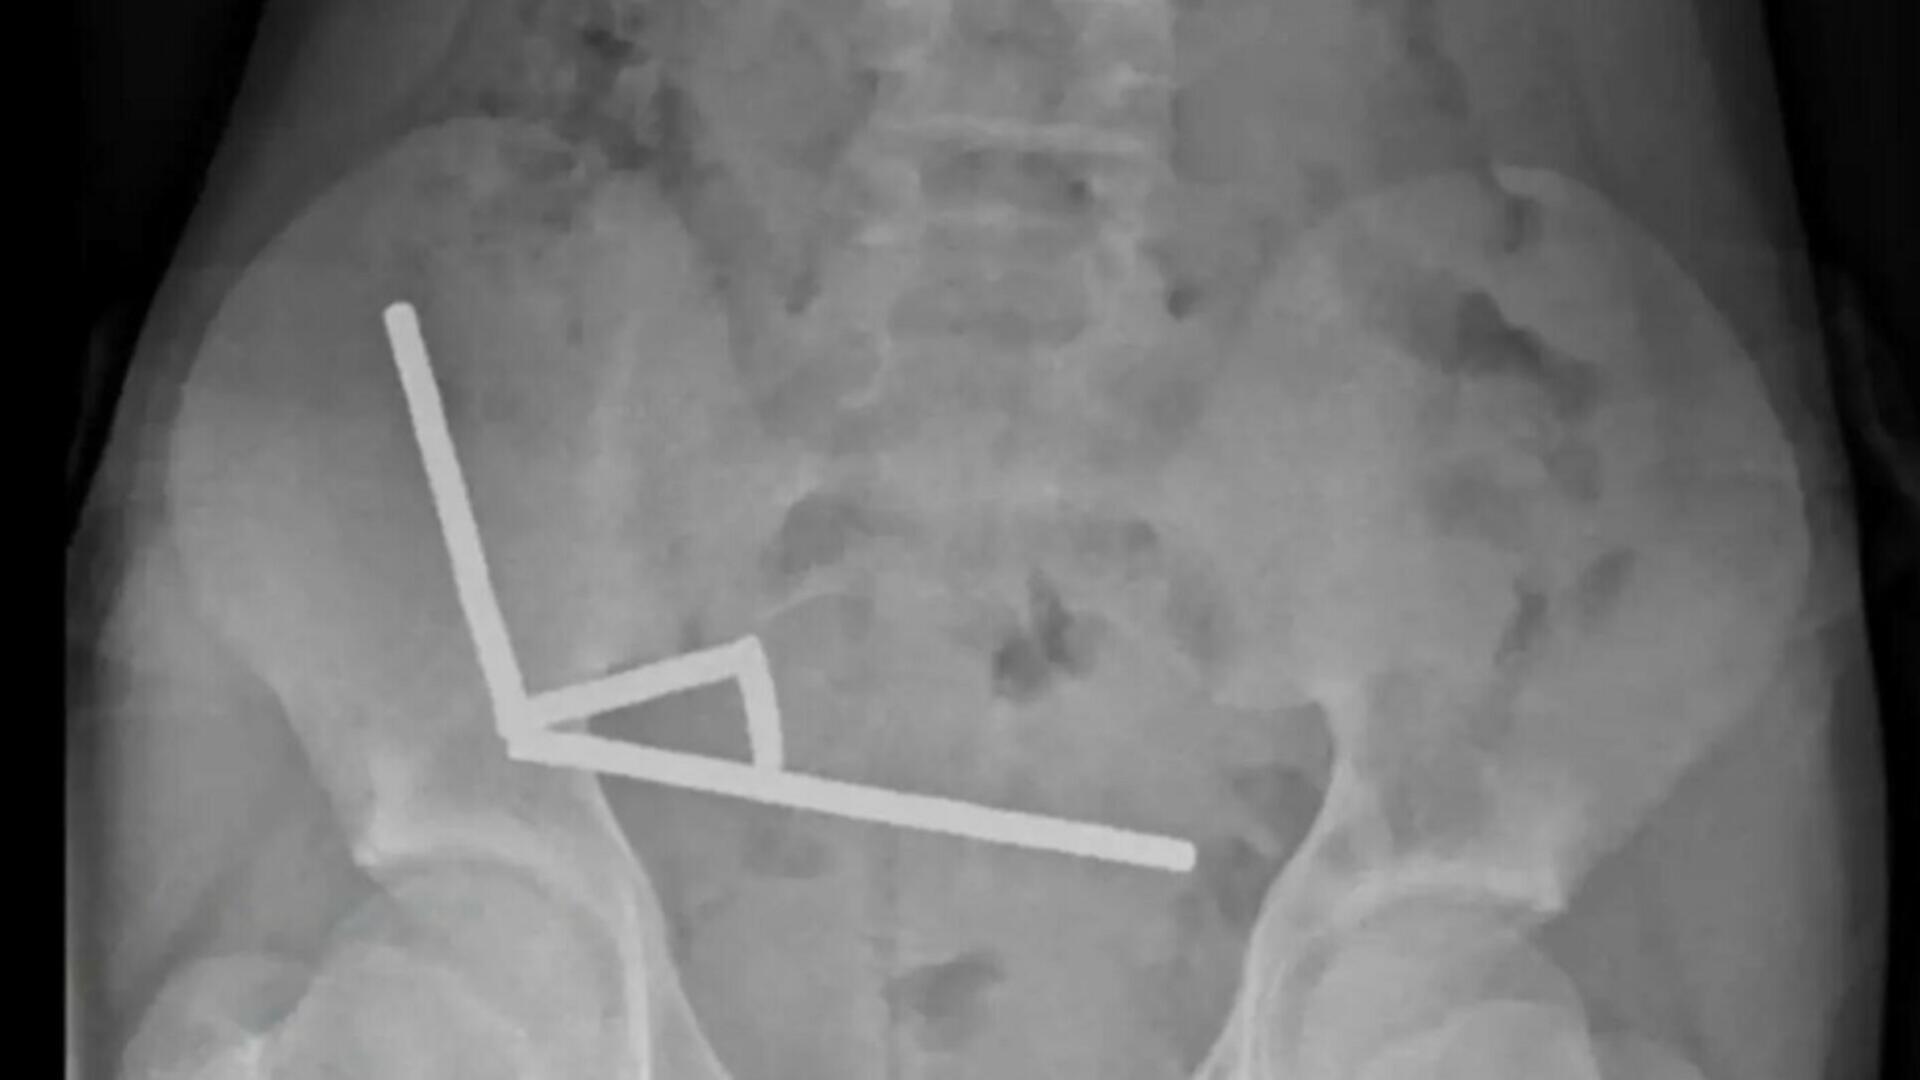

Potrivit raportului publicat în New Zealand Medical Journal, imaginile radiologice au arătat patru lanțuri magnetice prinse în diferite zone ale intestinului. Magneții, atrăgându-se între ei, au blocat circulația sângelui și au produs necroză intestinală — o complicație care i-a pus viața în pericol. Medicii au fost nevoiți să îndepărteze o porțiune din intestin pentru a salva pacientul.